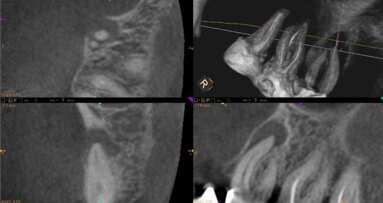

W 1985 r. W. Röntgen odkrył nowy rodzaj promieniowania i diagnostyka w medycynie nabrała nowego wymiaru. Zastąpienie kliszy czujnikami cyfrowymi ...